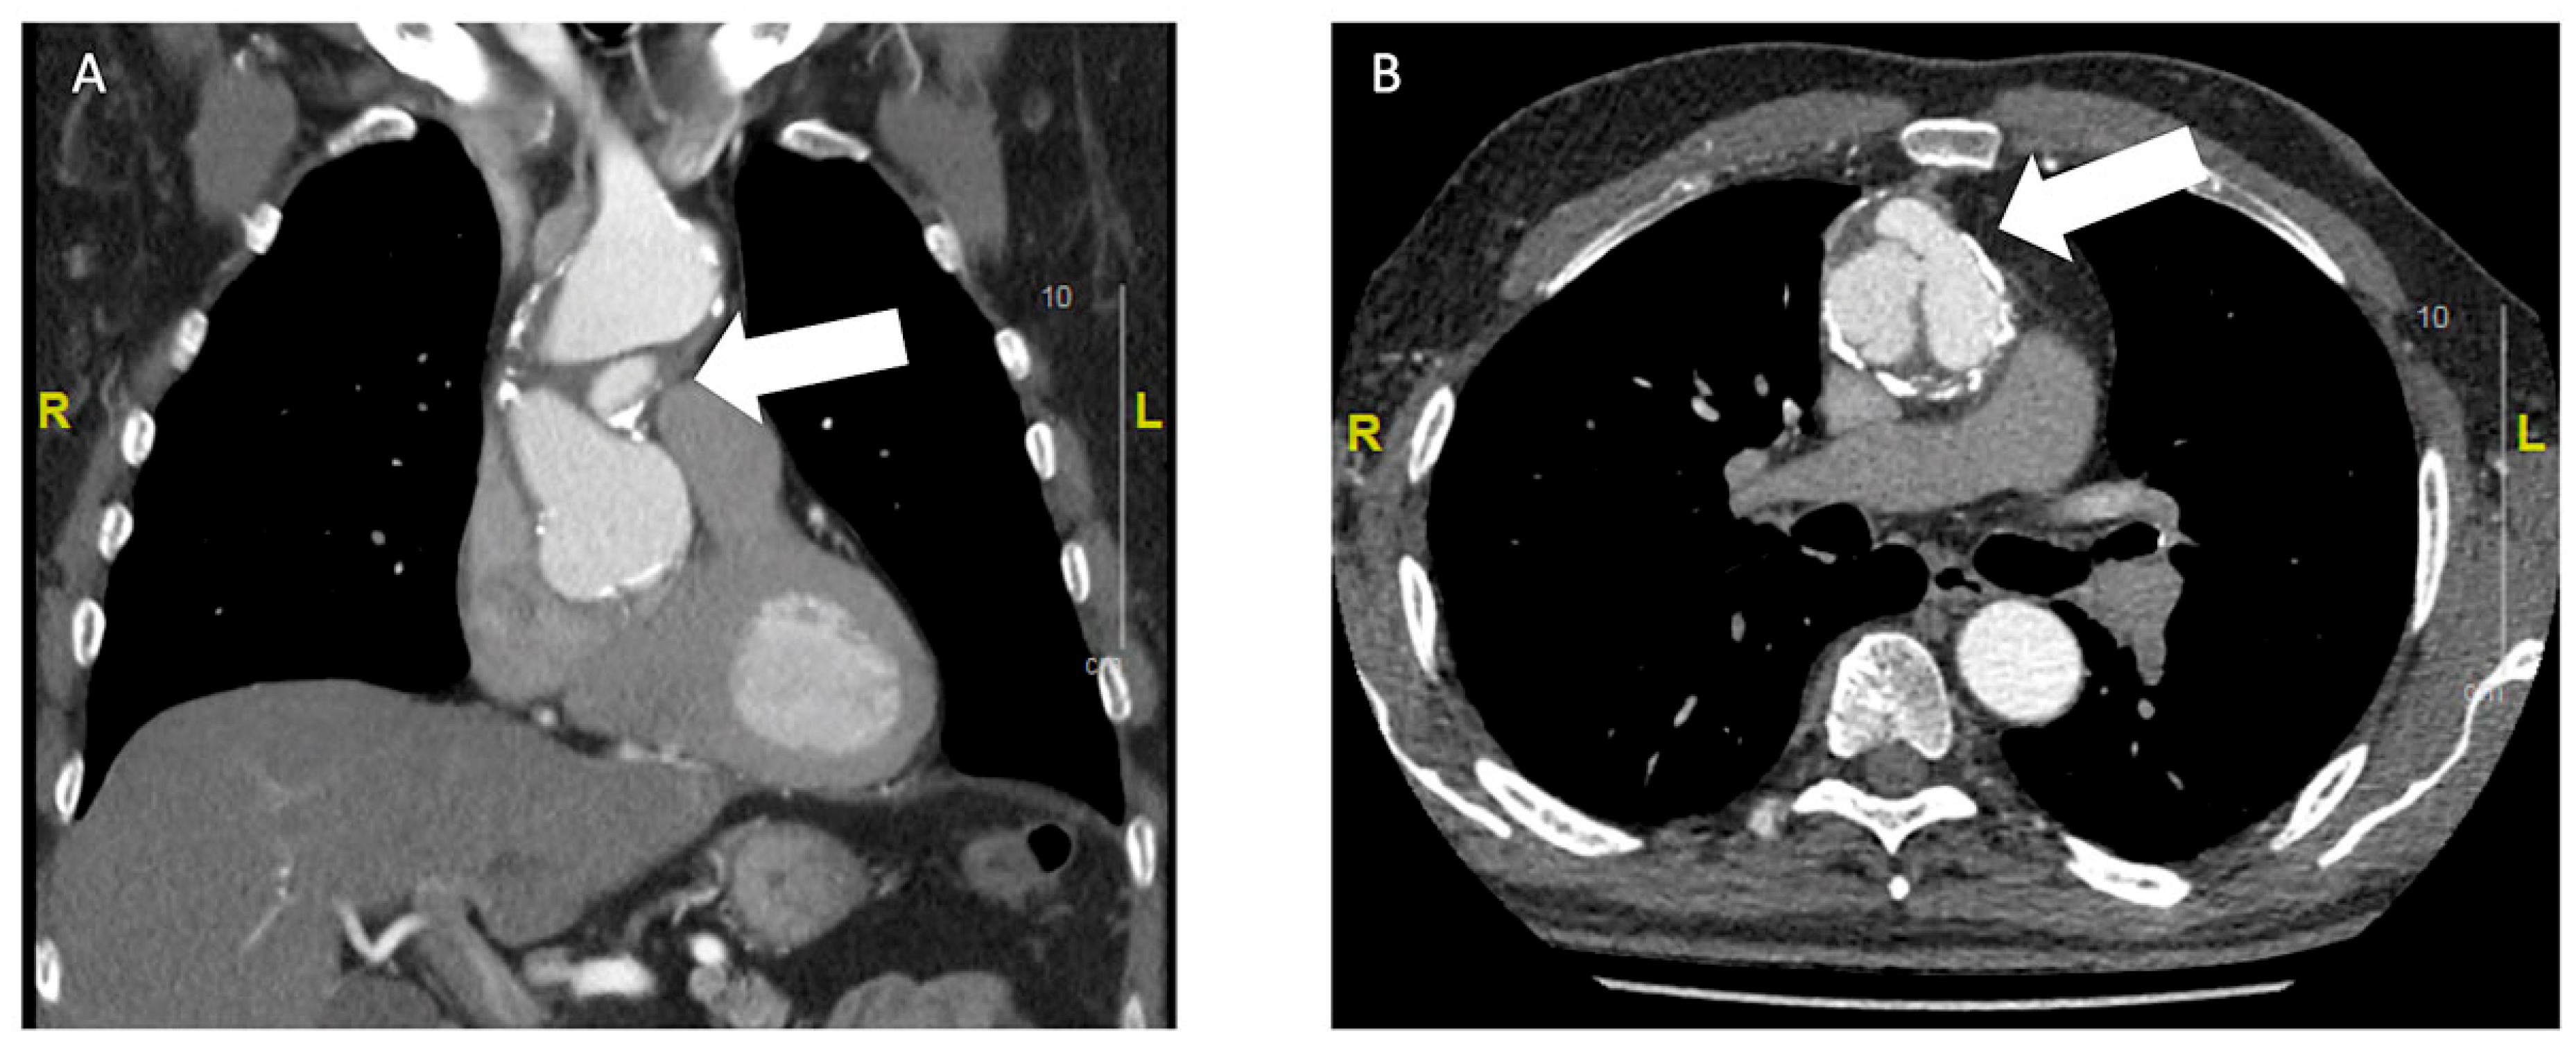

Bei einem 63-jährigen Patienten besteht ein Status nach mechanischem Aortenklappenersatz 1994 mittels St. Jude Medical© 25 mm bei kombiniertem Aortenklappenvitium, notfallmässigem Ersatz der Aorta ascendens mit 30-mm-Gefässprothese und Erhalt der Aortenklappenprothese im hypothermen Kreislaufstillstand bei Aortendissektion Typ A im Jahr 2001 und erneuter Reoperation bei Nahtaneurysmen mit Ersatz der Aorta ascendens und des Aortenbogens mit Haemoshield-Gefässprothese im Jahr 2003. Bei einer routinemässig durchgeführten Nachkontrolle durch den niedergelassenen Kardiologen wurde mittels transthorakaler Echokardiographie (TTE) ein perfundiertes Pseudoaneurysma im Bereich des proximalen Aortengrafts festgestellt (Abbildung 1). Daraufhin wurde der klinisch beschwerdefreie und hämodynamisch stabile Patient zur dringlichen Computertomographie (CT) in ein peripheres Spital überwiesen. Dort bestätigte sich der Verdacht eines Pseudoaneurysma im Sinne eines Nahthaneurysma (ca. 47 × 19 × 44 mm) ausgehend von der Aorta-ascendens-Prothese mit hochgradigem Verdacht auf Graftdehiszenz zwischen Ascendes- und Aortenbogengraft (Abbildung 2).

Abbildung 1. Nachweis des perfundierten Pseudoaneurysma (weisser Pfeil) in der echokardiographischen Kontrolle (A: parasternale lange Achse; B: mit Farbdoppler). Dabei zeigt sich die systolisch perfundierte Höhle vor dem Aortengraft.

Beim Patienten aus unserem Fallbericht war der Prothesenausriss ein Zufallsbefund im TTE 17 Jahre nach der letzten Operation. Hier bestand die Nachkontrolle aus einem jährlichen Kontrolltermin beim niedergelassenen Kardiologen, bei dem zur Diagnostik jeweils ein TTE durchgeführt wurde. In einem solchen wurde auch das Nahtaneurysma nachgewiesen und die weitere Diagnostik und Therapie in die Wege geleitet.